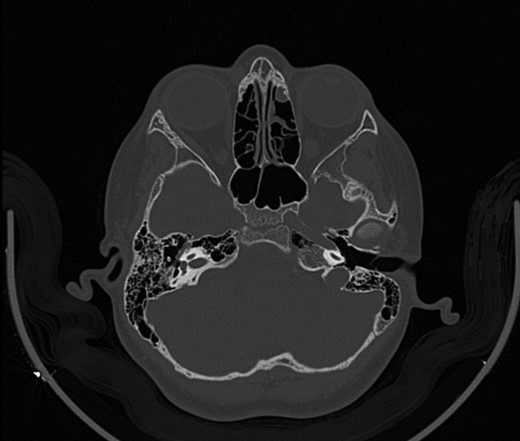

A 14-year-old male patient presented to the ENT clinic with bilateral hearing loss with no other otolaryngological symptoms. History from the patient stated a road traffic accident (RTA) 12 months ago. Meanwhile, the patient had no hearing problems prior to the RTA. Furthermore, detailed history of the accident revealed that the patient had no apparent skull injuries while pure tone audiometry (PTA) on presentation revealed bilateral conductive hearing loss and auditory brainstem response revealed right mild hearing loss and left moderate hearing loss. As a result, he was fitted with hearing aid for four months after presentation and was not compliant to it on the long-term. The patient is a non-smoker and is medically free with normal developmental milestones and negative family history of hearing complaints. Local examination of the ear revealed intact but minimally retracted tympanic membrane bilaterally. PTA was done in 2014 revealed right mild to moderate mixed hearing loss and conductive hearing loss at low frequency (Table 1). Meanwhile, the left ear had mild to moderate sensory hearing loss at high frequency (Table 2). The speech audiogram results show equal canal volume in both ears, less tympanometry pressure on the right ear and less compliance on the right ear (Table 3). The CT showed that both ossicular chains are deranged, and bilateral abnormal ossicles with no fracture or mass (Figures 1–3).

Figure 1:

CT mastoid, deranged right side ossicular disruption.